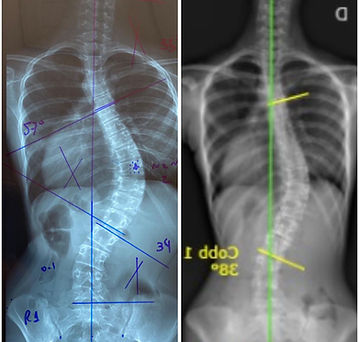

"Tenho 17 anos e sou musicista. Eu descobri minha escoliose quando tinha 13 anos e foi um grande susto! Me consultei com um médico e ele já tinha nos falado que precisaria de cirurgia, mas para mim, isso não era uma opção. Minha curvatura progrediu de 42º a 57° em um ano, neste período fiz fisioterapia com exercícios gerais, nada especifico.

A cirurgia parecia algo inevitável, mas fiz o tratamento especifico por 6 meses, batalhando muito e quando retornei, minha escoliose tinha melhorado, chegando em 38°. Cada caso é um caso, mas minha história me mostrou que nada é impossível."